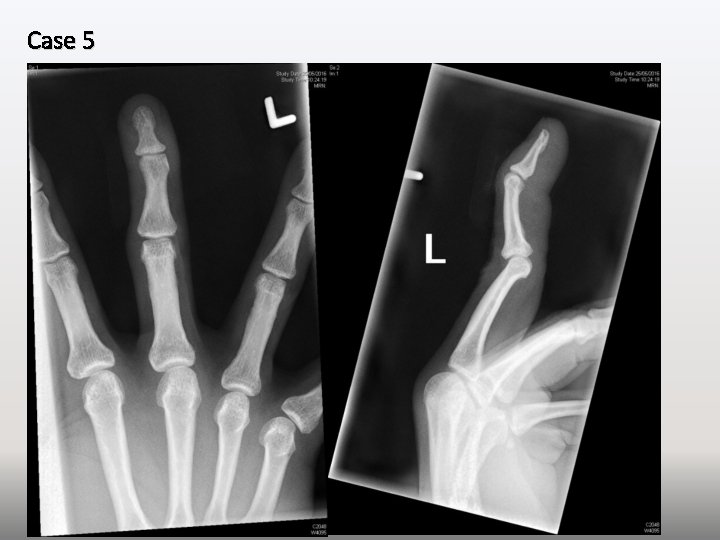

Case 5 A 42 -year-old man sustained crush injury over left middle finger at

Case 5 A 42 -year-old man sustained crush injury over left middle finger at work. A 2. 5 cm long laceration was seen over dorsum of left middle finger near DIPJ. X-ray was performed.

Case 5 1. What are the x-ray findings? (3 marks) 2. What is the

Case 5 1. What are the x-ray findings? (3 marks) 2. What is the diagnosis? (1 mark) 3. What is the underlying pathology of his condition? (2 marks)